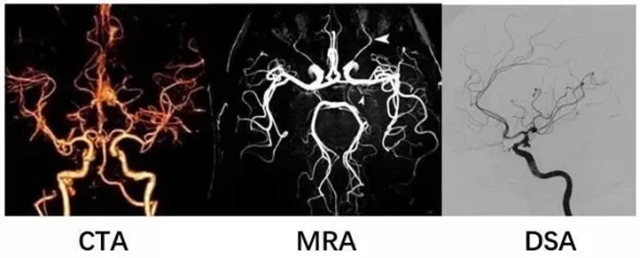

脑动脉瘤破裂前多无症状,主动筛查是关键!目前主流的3种检查各有侧重,帮你理清选择逻辑:

1、MRA(磁共振血管成像)

优点:无创、无辐射,不用打针造影剂,是高危人群首选筛查手段,也适合术后长期复查;

缺点:对小于3mm的微小动脉瘤可能漏诊。

2、CTA(CT血管成像)

优点:检查速度快、图像清晰,能明确动脉瘤和骨骼的位置关系,是常用的无创确诊检查;

缺点:需注射含碘造影剂,有极少数过敏风险,且有X线辐射。

3、DSA(全脑血管造影术)

优点:诊断的“金标准”,能动态、清晰显示血管细节,是制定治疗方案(尤其介入治疗)的最终依据;

缺点:属于有创操作,费用较高,一般在MRA/CTA发现异常后使用。

高危人群先做MRA初步排查,发现问题再用CTA确认,治疗前需DSA精准评估。